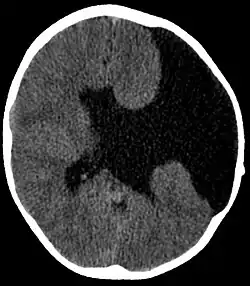

Axial CT scan showing schizencephaly in a 6-year-old child

Schizencephaly (from Greek skhizein 'to split' and enkephalos 'brain')[1][2] is a rare birth defect of the brain, characterized by abnormal clefts lined with grey matter that form the ependyma of the cerebral ventricles to the pia mater. These clefts can occur bilaterally or unilaterally. Common clinical features of this malformation include epilepsy, motor deficits, and psychomotor retardation.[3]